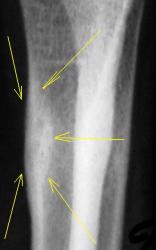

А с этим (помечено стрелками), что будем делать?

Коллеги! меня тоже смущает участок, выделенный Валентином Львовичем стрелочками. Имеются округлой формы, мелкие участки перестройки костной ткани литического типа. Кортикальный слой муфтообразно утолщен с периоссальной реакцией. А нет ли там объемного образования?

Меня тоже смущает, и очень. Отправляйте к детским онкологам, пусть они контролируют. Основание: диафиз лучевой кости бульбообразно расширен ("поддут"), структура кости уплотнена муфтообразно/"пояском", менее выраженные, чем по переднему стенке кости, но аналогичные изменения отмечаются и по задней стенке диафиза, плюс периостальная реакция в прямой проекции.